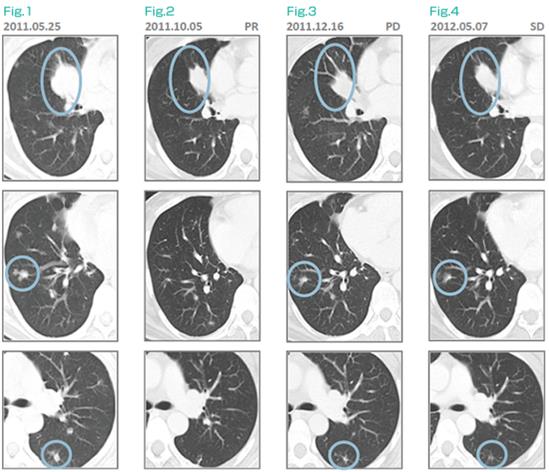

39岁女性,无吸烟史,2011年4月诊断EGFR阳性肺癌,胸椎转移,cT4N0M1b。6月开始口服厄洛替尼(特罗凯),10月CT检查略有缓解,但已发生病理性骨折,无法站立。11月开始在濑田接受αβT细胞(制备过程中洗除部分Treg)+厄洛替尼治疗,12月CT发现肿瘤进展,诊断厄洛替尼耐药。此时按照标准疗法应该停止厄洛替尼,改为化疗,但患者不同意。制剂继续接受厄洛替尼+细胞治疗,在2012年1月、2月、5月、6月的CT评估中,肿瘤保持稳定(SD)。

患者反感化疗,且taptap点点网页登录见效慢,这位患者选择了继续细胞疗法,得到了较长时间的SD。另有文献证实,其实化疗+免疫细胞疗法也可能有效: Iwai K, Soejima K, Kudoh S, et al.: Extended survival observed in adoptive activated T lymphocyte immunotherapy for advanced lung cancer: results of a multicenter historical cohort study. Cancer Immunol Immunother.,DOI: 10.1007/s00262-012-1226-4,Mar 16,2012